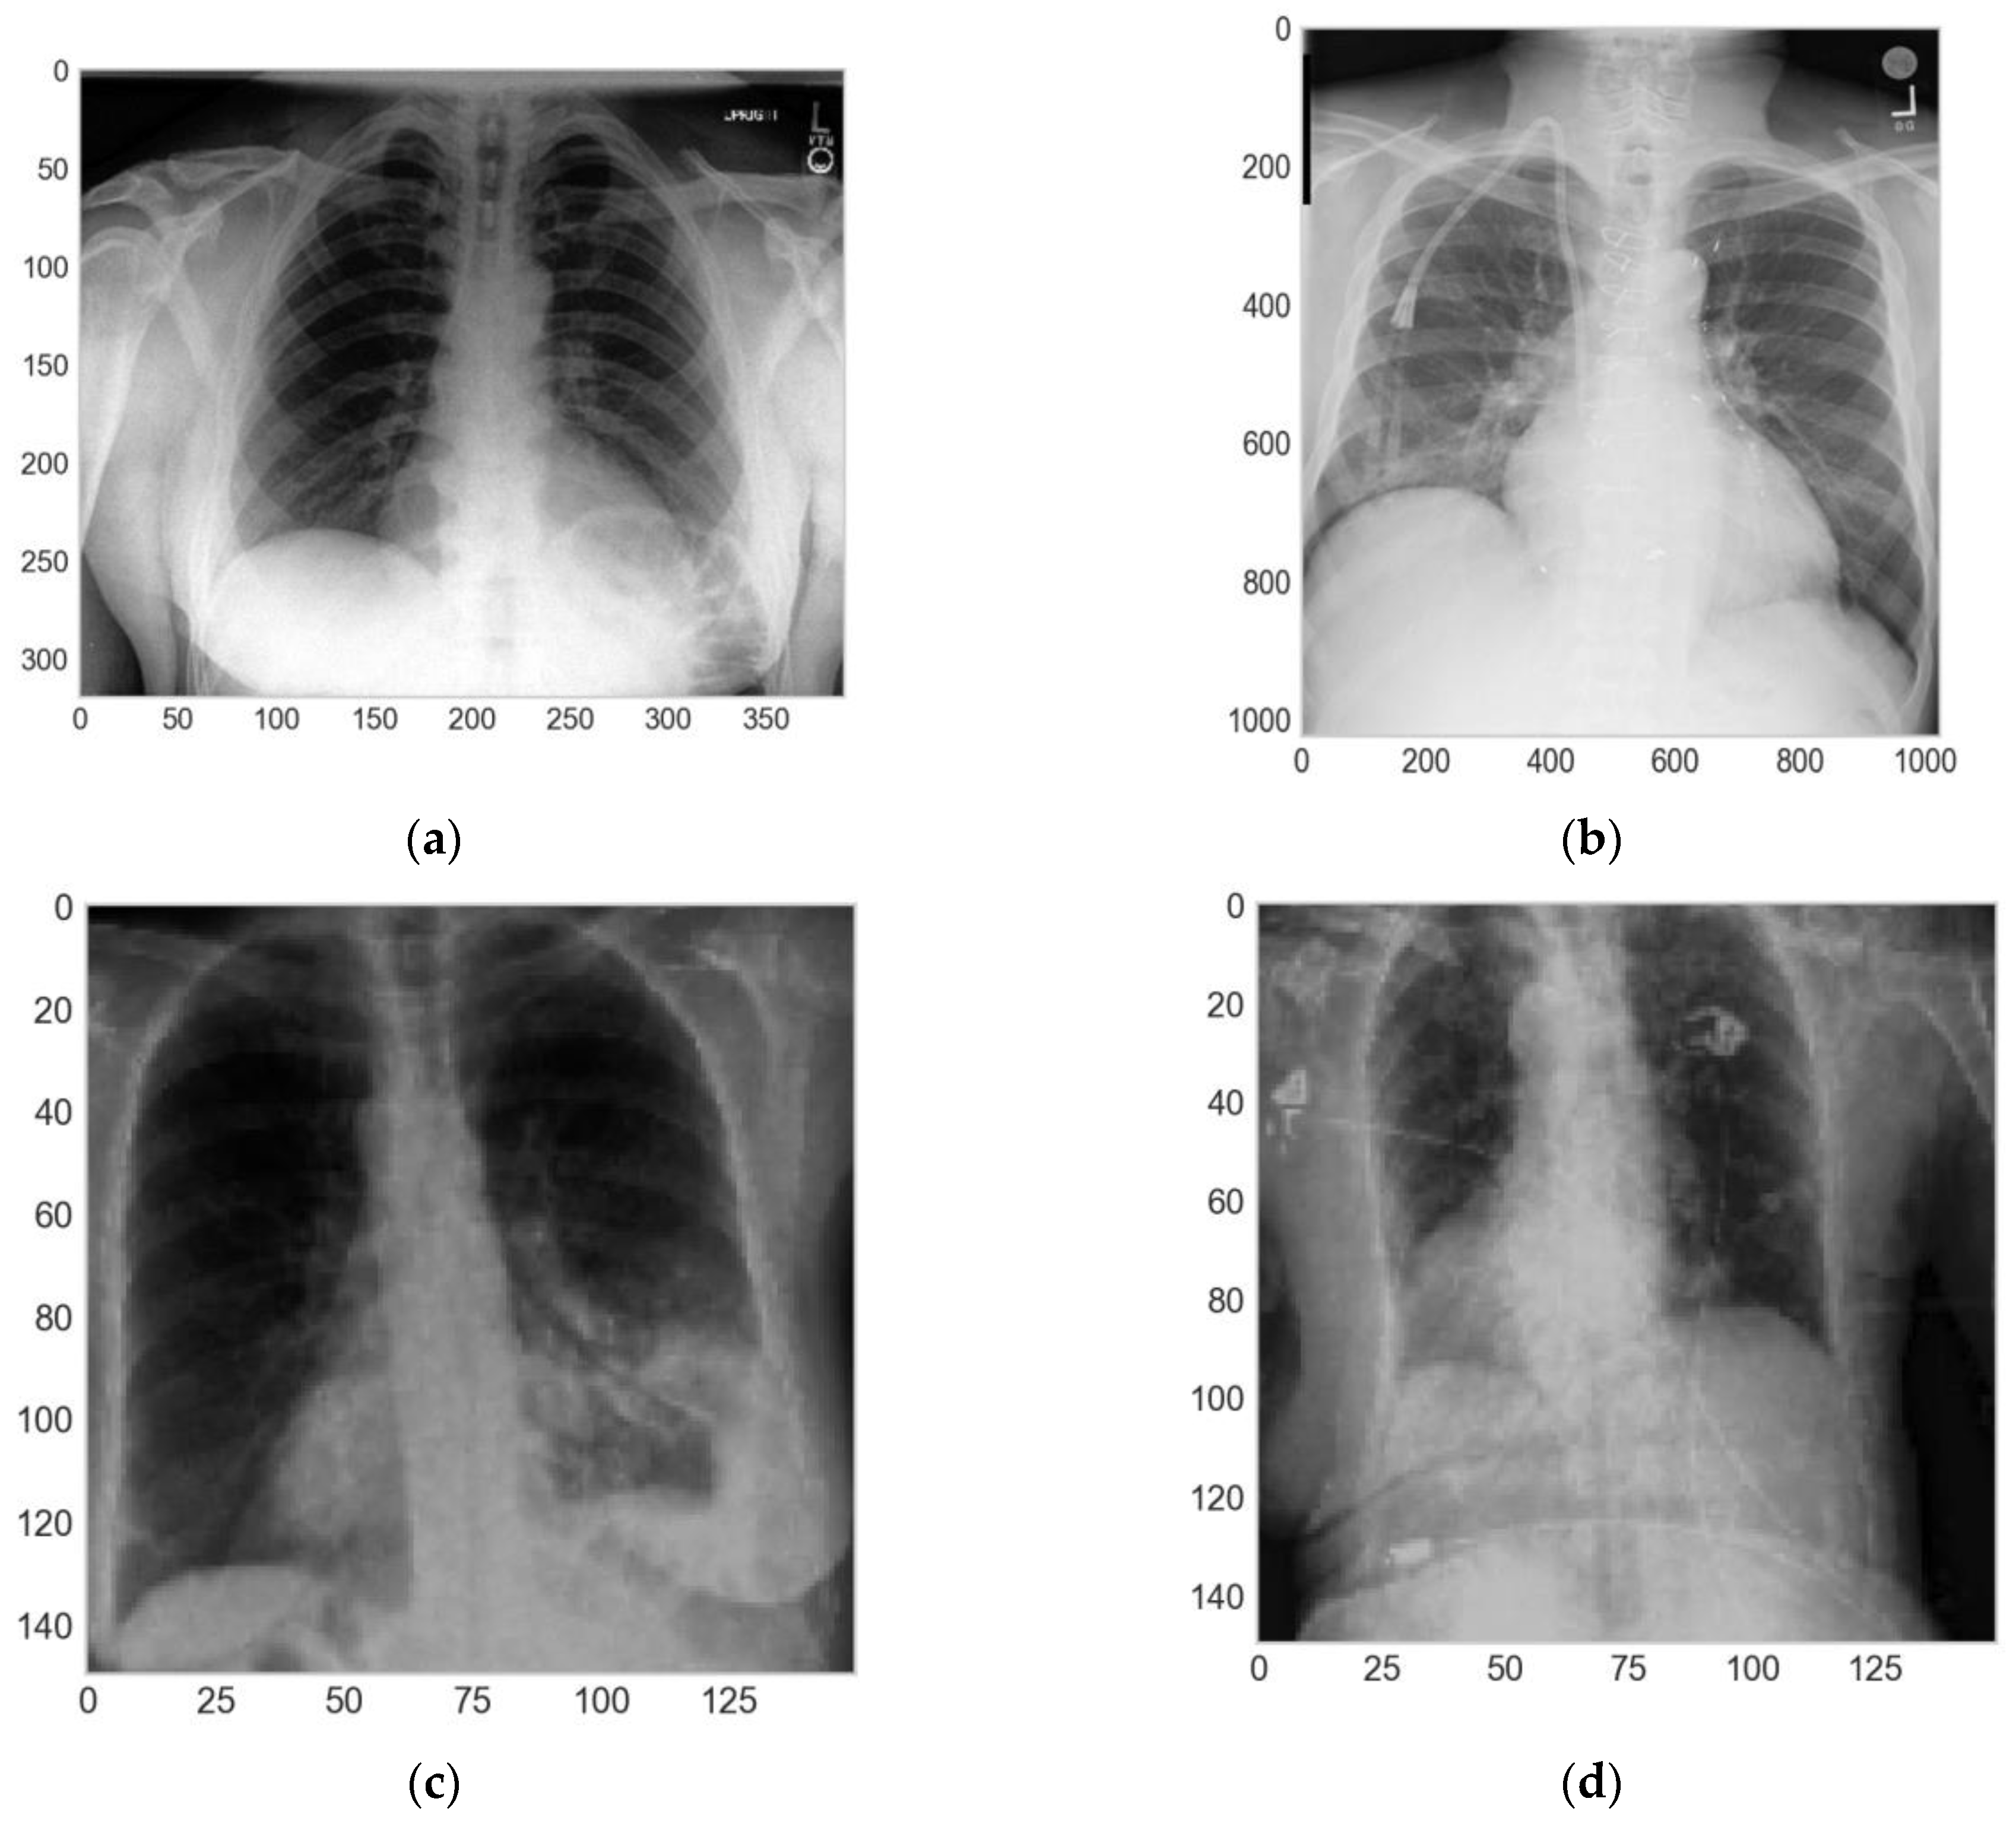

In this phase, first, we divided the sample into three groups, i.e., training, validation, and test sets, with the ratios of 80%, 10% and 10%, respectively, using the method in [28]. Then, we applied a resizing of the height and width of each image to 150 × 150 pixels. Second, we used the method in [29] for the training and validation sets. The transformations applied were the zoom-in, horizontal flip, rotation between 0 and 5 degrees, and normalization of each pixel of the different images, dividing every pixel of the images by 255.0 to achieve 0 as the minimum value and 1 as the maximum value (Figure 3).

Figure 3.

Comparison of the original and augmented images: (a) original image from CheXpert dataset; (b) original image from ChestX-ray14 dataset; (c,d) augmented images after preprocessing.